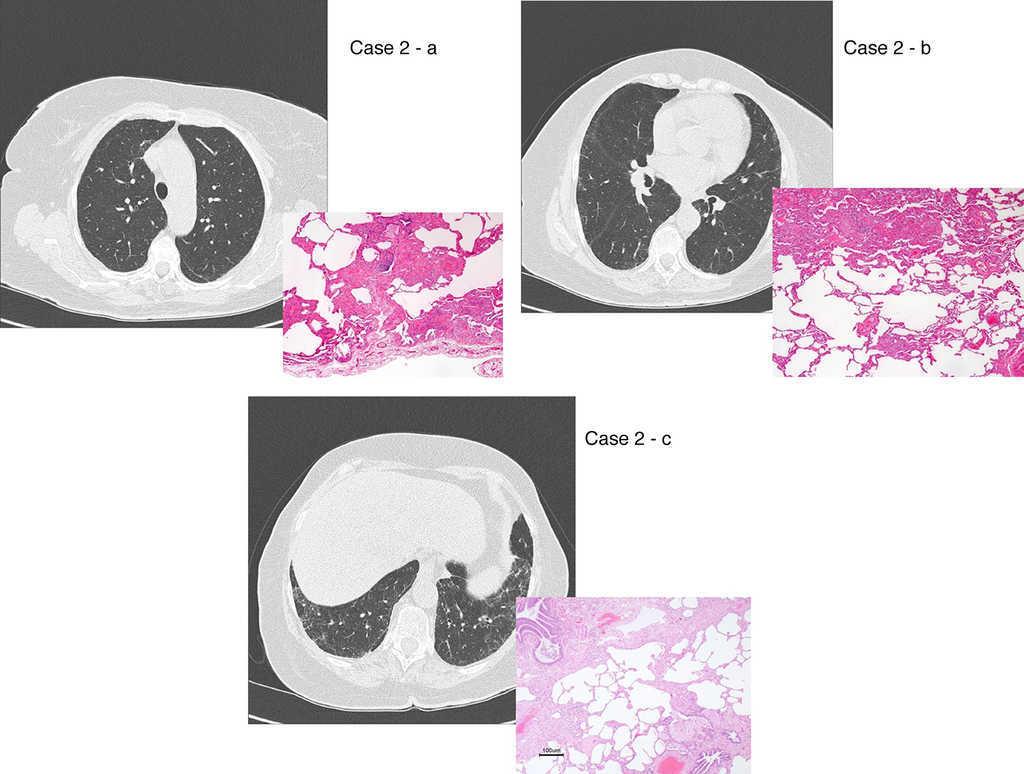

Figure 2. UIP/IPF identification in HRCT and histopathology. Case 1 – a: Common histopathological features of UIP/IPF consisting in honeycombing as a result of subpleural airway spaces confluence with bronchialization of epithelium where mucus cells may be predominant. HE 100×. Case 1 – b: The previous image aspects are revealed by higher production of mucus occupying the new formed subpleural smaller confluent airspaces. HE 100×. Case 1 – c: The interstitium intermingling honey-combing loses elastin fibres and is represented by fusiform cells, either fibroblasts or miofibroblasts, with collagen deposition. Elastin-van Gieson 100×. Case 2 – a: Irregular confluent air spaces with typical subpleural localization of UIP/IPF honeycombing with interstitium enlargement by fusiform cells. HE 100×. Case 2 – b: The adjacent lobular parenchyma accentuate histopathological heterogeneity, starting by overinflation and pseudo emphysema morphology. HE 100×. Case 2 – c: The lobular histopathological remodelling aspect of fibrosis enlarging alveoli septae till central bronchiolo-vascular axes and alveolar bronchialization. HE 100×. Case 3 – a: Small subpeural confluent air-spaces with bronchial-like epithelium and juvenile foci of fibroblasts in myxoid matrix; lymphocytes are seen. PAS 200×. Case 3 – b: UIP/IPF heterogeneous morphology in airspaces confluence with subpleural preponderance and committing the whole lobule. HE 100×.

The histological pattern of UIP must present: 1 – marked fibrosis/architectural distortion, with or without honeycombing in a predominantly subpleural/paraseptal distribution; 2 – patchy involvement of lung parenchyma by fibrosis; 3 – fibroblast foci; 4 – absence of features against a diagnosis of UIP suggesting an alternate diagnosis1, 51 (Figure 2).